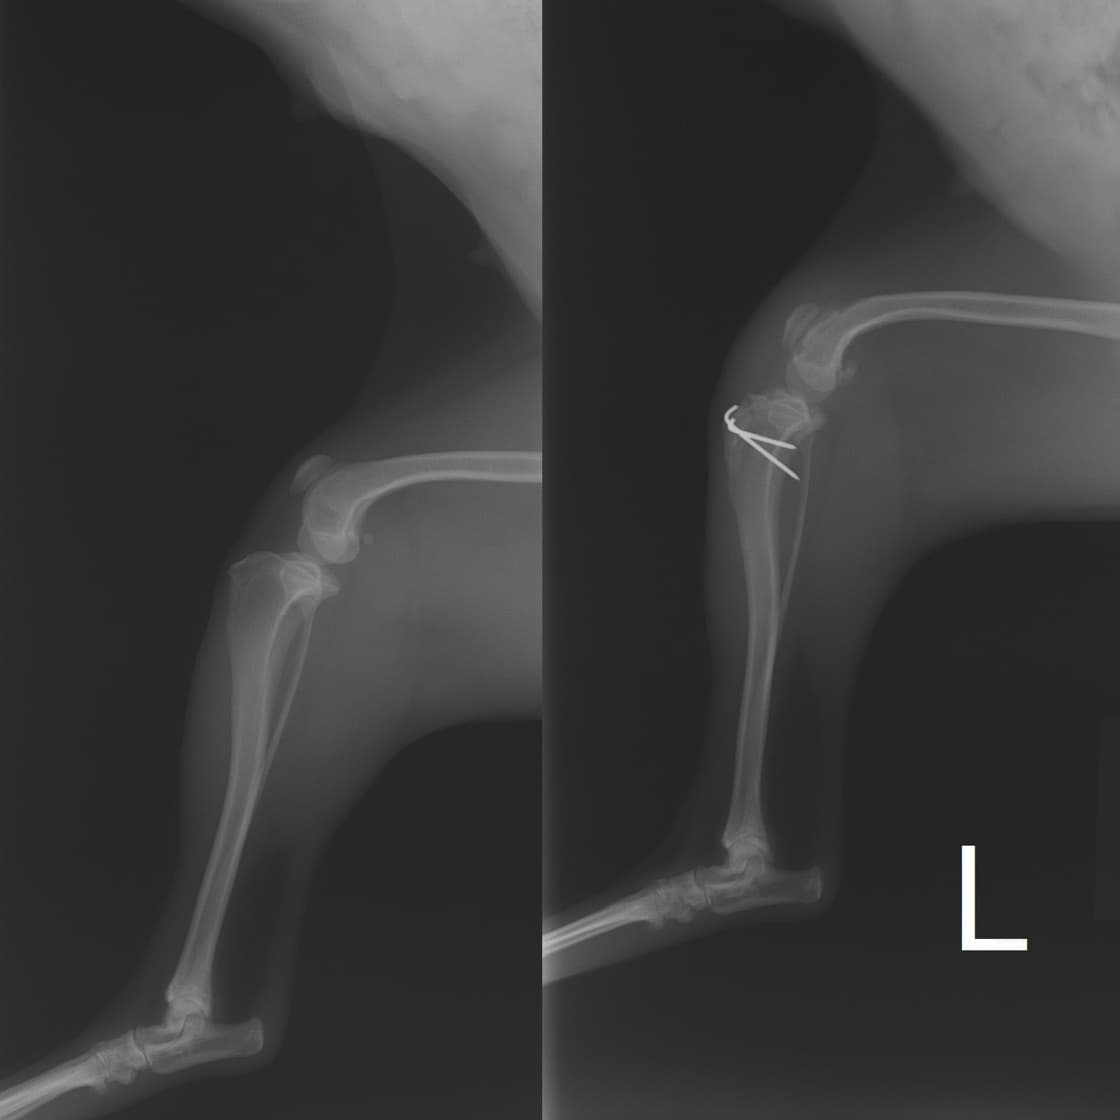

■ 症例24 キャバリア 7か月

左右膝蓋骨内方脱臼(左:グレードⅣ 右:グレードⅢ)

以前から左右後肢の跛行が認められ、整形外科学的検査・レントゲン検査により左右の膝蓋骨脱臼が認められた。症状が重度である左膝の膝蓋骨脱臼整復術を行った。外科手技は縫工筋及び内側広筋の解放、脛骨粗面の外側転位、滑車ブロック形造溝術、内外側関節方の縫縮を実施した。術後一か月時点で、左の膝蓋骨は安定しており経過は良好である。

本症例は成長期における重度の膝蓋骨脱臼であり、術後の再発の可能性もあるため、経過をしっかりと観察していく必要がある。また、今回手術を実施していない右膝に関しても経過を観察し、手術を検討していくこととする。